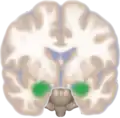

Frontal view of the amygdala in an average human brain

Amygdala highlighted in green on coronal T1 MRI images